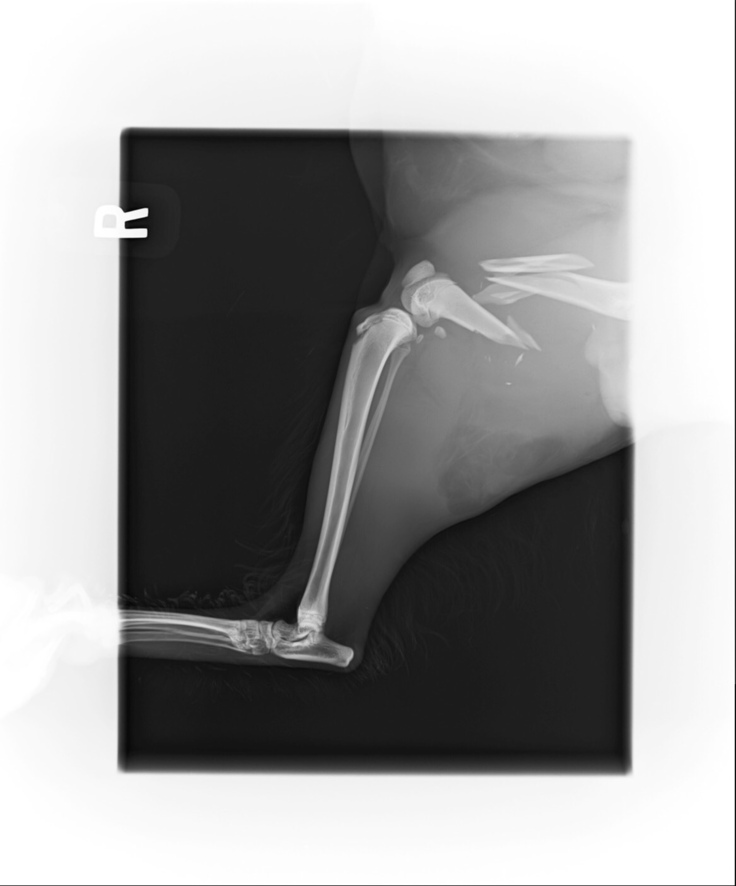

手術結果は切開してみると、骨折が思いのほか酷く膝下まで達していたので、処置の施しようが無く右脚脱脚となってしまいました。

現在安静を保つ為に、桃ちゃんは入院中ですが抜糸を終えております。面会にも行っております。

まだ、左脚股関節のピンが入っていて今後も通院の必要があります。

心配していた残った左足股関節のピンで留めていた部分が外れて再手術になりました。

ピンを抜き骨頭を切除する手術になります。